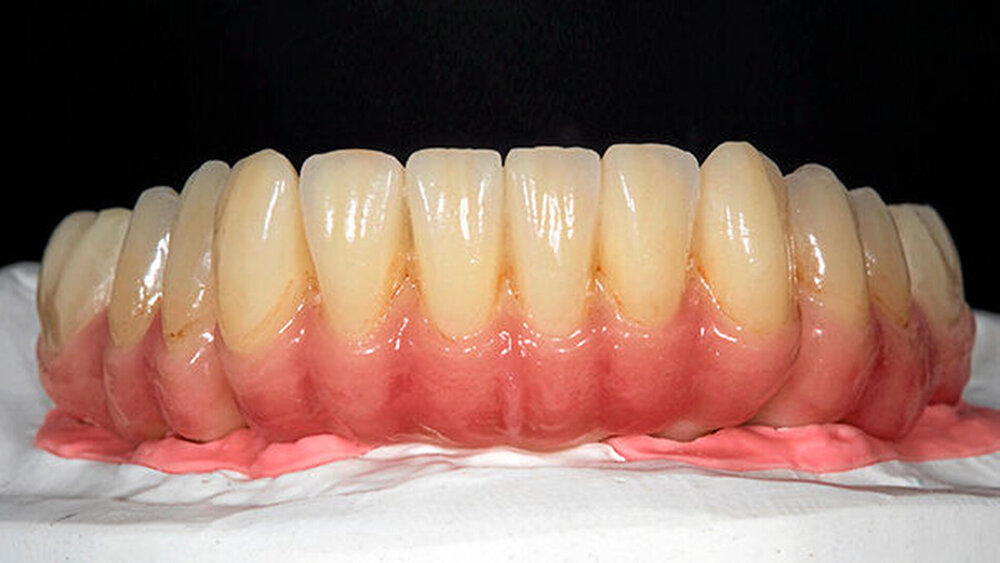

Die größte Herausforderung dabei, trotz 3D-Planung und Bohrschablone, ist es, die rote Ästhetik im Frontzahnbereich zwei bis drei Monate nach der Freilegung vorhersagbar zu kalkulieren. Da spielen viele Einflussfaktoren eine Rolle, eine zu dünne vestibuläre Knochenlamelle, der Stressfaktor „axiale Bewegung“, der diese dünne Knochenlamelle schnell überfordern kann etc. Zieht sich das rosafarbene Volumen zurück, ist das natürlich für den Zahntechniker schwierig zu handeln. Eine rosafarbene Gingivakappe, die aus Keramik aufgebrannt wird, kann helfen. Das ist zwar ein Kompromiss, aber ein Kompromiss, mit dem die Patienten leben können.

Aufwendige Augmentationen. Nach umfangreichen Knochendefekten im anterioren Bereich müsste der Knochen aufgebaut werden, Bindegewebstransplantate etc. verbessern die Situation weiter. Doch Patienten möchten irgendwann auch einmal die Behandlung abschließen. Und Zahntechniker meistern die keramische Gingivakorrektur wirklich großartig. Auch wenn es für den Behandler wenig zufriedenstellend ist, es gilt mit adäquatem Aufwand ein gutes Ergebnis zu erzielen.